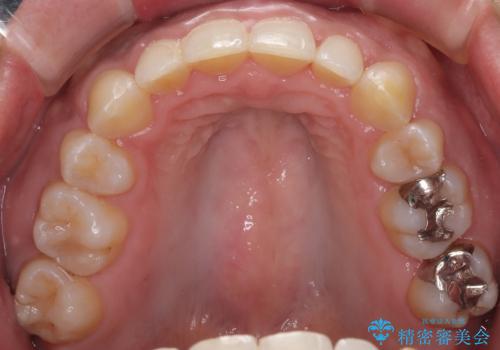

抜歯矯正で口が閉じやすく|ディープバイトと叢生を改善した症例

- 下顎前歯部には叢生が認められ、口を自然に閉じにくい状態でした。また、噛み合わせが深い「ディープバイト」の状態で、見た目だけでなく将来的な奥歯への負担も懸念されました。

口元の突出感を改善するため、上下左右の小臼歯4本を抜歯する矯正治療を計画しました。

「矯正装置が目立つのは避けたい」というご希望があったため、プラスチックブラケット+コーティングワイヤーを使用した審美装置を選択しました。